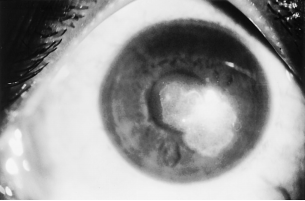

The conjunctiva may show a fine papillary reaction. Keratitis can present as a nonspecific punctate epitheliopathy or an ulcer with margins studded with yellow white pinhead sized superficial infiltration (Figure. 1).[1][16] Patchy infiltrations are predominantly anterior stromal with involvement of the epithelial and subepithelial tissues.[16] These infiltrates often present in a classical wreath like pattern with satellite lesions (Figure. 2).[1][16] Infiltrates are usually situated in the midperiphery of the cornea adjacent to the sites of minor corneal trauma or abrasion.[16]